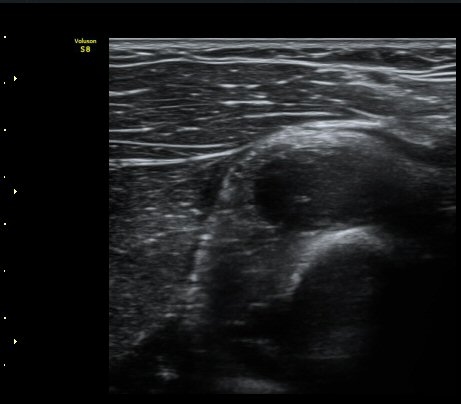

¼ÒµÎ Ⱦ´Ü¸é°Ë»ç¿¡¼­ ¿ä°ñ½Å°æ Èİñ°£½Å°æÀÌ Á¤»óÀûÀ¸·Î °í³ªÂûµÈ´Ù(±×¸² 1).

ŽÃËÀÚ¸¦ ¿ä°ñµÎ ºÎÀ§·Î À̵¿ÇÏ´Ï ¿ä°ñµÎ Ç¥Ãþ¿¡ Àú¿¡ÄÚ ³¶Á¾ÀÌ °üÂûµÇ°í ³¶Á¾ÀÇ ¿ÜÃø¿¡¼­

Èİñ°£½Å°æÀÌ ¾Ð¹ÚµÇ°í ÀÖ´Ù(±×¸² 2).